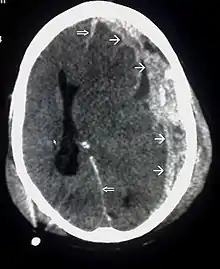

| CT scan showing cerebral contusions, hemorrhage within the hemispheres, and subdural hematoma. There is also displaced skull fracture of left transverse parietal and temporal bones.[2] | |

The preferred radiologic test in the emergency setting is computed tomography (CT): it is quick, accurate, and widely available.[80] Follow-up CT scans may be performed later to determine whether the injury has progressed.[27]